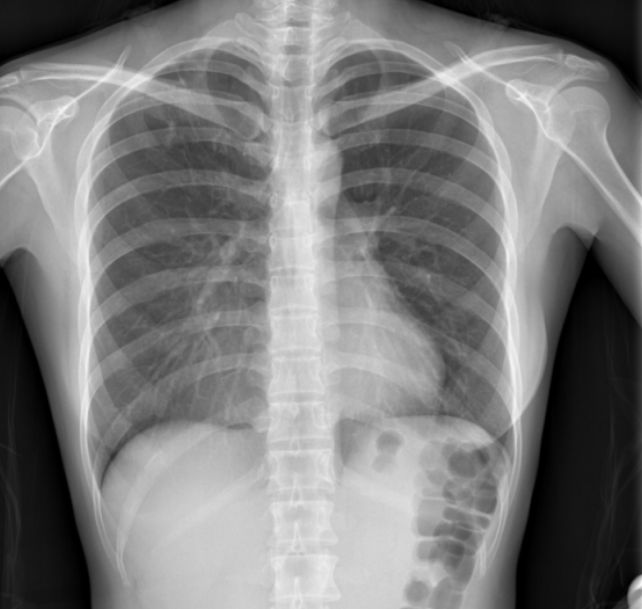

但是我还是想分享付国助老先生医治我肺结核痊愈的医案,我没有针对肺结核做过治疗,就是调理身体,但是前两个月遇巧检查血液,已经没有结核菌了。我最开始被诊断为肺结核的时候,(那个时候还不太了解中医)我想肺结核是传染病,中医肯定没有办法,只能靠西医。 2015 年3 月,当时在香港读研。因为经常心慌,所以去了校医院检查,结果校医检查心电图后让我去急诊室。急诊室检查后,让救护车把我拉到了肺专科诊室。医生说肺部感染,开了一个星期的药,吃了没有任何改善,于是说是肺结核,每天必须到诊室吃药。 2015 年 6 月,检查了无数次,支气管镜也检查了,CT也做了,可是肺部阴影没有任何变化。当时我失去了食欲,白天精神不好,晚上也睡不着。因为实在吃不下东西,所以买了搅拌机把食物全部打碎吃。虽然依然没有食欲,但是也只能强迫自己吃。同时很想吃冰淇淋和蛋糕。所以虽然已有五年半全素食的我,也最终忍不住吃了冰淇淋和蛋糕。 最后,我觉得这样下去实在不是办法,于是回到濮阳托人找关系找到了付国助医生诊治。吃了几天中药之后,食欲稍微有点好转。那位付国助医生说,肺部阴影应该就是湿气。西医说传染,为什么有的人会被传染,有的人不会。空气中随时都有很多细菌,关键是看自己的身体有没有足够的抵抗力去抵御这些细菌。